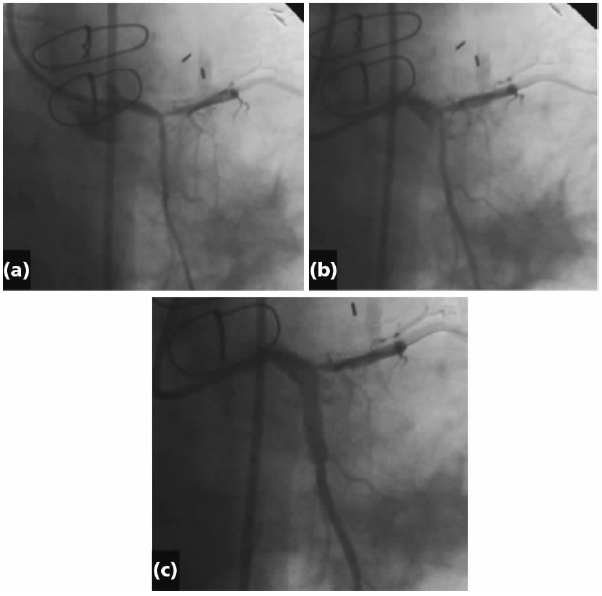

图15.1 导管导致左主干夹层的解剖。(a)注射造影剂示出左主干与左旋支。(b)进入处出现夹层并向远端延展。(c)完全夹层出现,阻遏流向远端的血流,在左旋支中段停止。

顺向延展夹层可能在之前放置支架的区域终止,由于三层血管壁被支架紧压,或在具较大侧支的分叉处终止。如果夹层在包裹在房室沟中的左旋支(LCX)近段或中段发生,其一般可能不会向远端进展太远。然而,由于夹层被限制在紧张的空间中,其对于真腔的侵占更为严重(图15.1)。

左主干开口处操作或前降支开口处介入所致。左主干与前降支呈锐角,在球囊扩张处理前降支开口处病变并部分覆盖左主干时,是左主干夹层的危险因素。通常对于左主干损伤的处理是搭桥手术。然而,在等待急诊手术的过程中使患者保持稳定非常必要。在美国,对于大多数操作者来说,无保护左主干PCI并非常规操作。即使如此,为拯救生命,急性闭塞的左主干需要被紧急打开,类似于心包填塞时的心包腔穿刺。策略是要在插入临时起搏器与IABP前就打开左主干。全部急救操作需要在几分钟内完成,以防血流动力学紊乱、休克或死亡的发生。一旦患者稳定,可以考虑是否行搭桥手术(见图15.1)。